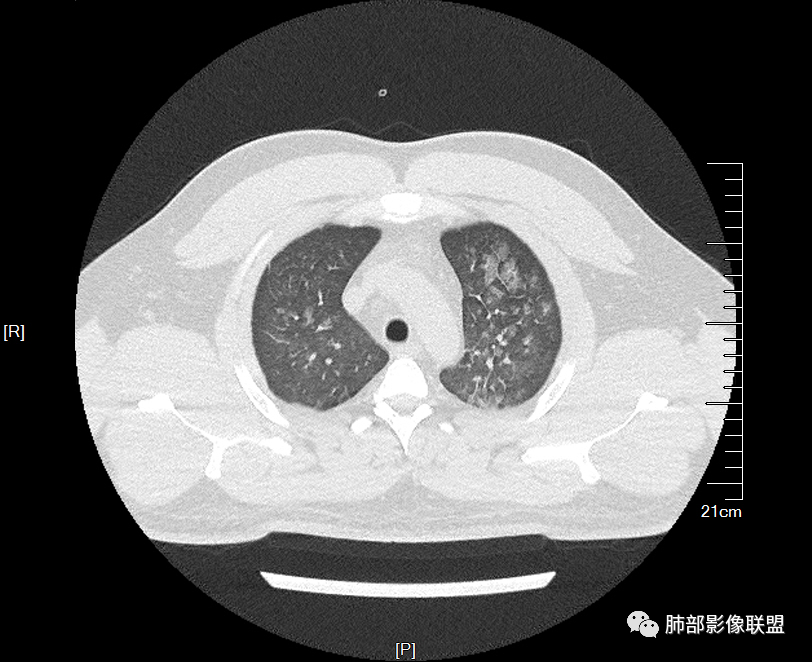

双肺多发弥漫性磨玻璃结节影,大小不一,形态不规则,部分融合,支气管未见明显扩张,部分血管束略增粗,叶裂胸膜增厚,临床有痛风,左足痛6天,考虑:1:痛风结节(一般实性结节,很少磨玻璃结节影)2:血管炎?3:病毒性肺炎(水痘-疱疹肺炎?)

年轻男性,既往血肌酐升高,左足痛六天入院,有痛风及高血压病史。CT示双肺多发磨玻璃结节影,不规则,部分融合成团或片状,小叶间隔增厚,以双下肺为明显,叶间胸膜亦见增厚。考虑为1.Good-Pasture综合征。2.病毒性肺炎?3.肺水肿?

男32岁。既往曾发现血肌酐升高.此次因左足痛6天入院。有痛风、高血压病史。两肺弥漫性的病变,小片状或者结节状为主病变,小叶中心分部为主,边界不清。心影比较饱满,肝实质密度均匀的降低。考虑为肝损害的影像学改变。综合考虑多功能脏器的损害,肺部损害肺泡炎?肺水肿?或病毒性的肺炎?

年轻男性,痛风史,高血压史,肌酐高,左足痛6天入院。胸CT:双肺多发弥漫性磨玻璃结节影,大小不一,部分融合,上中下肺都有,中内带多,胸膜下少。部分血管束略增粗,小叶内间隔、小叶间隔增厚,下肺明显,左室大。叶裂胸膜增厚。临床有痛风,左足痛6天,考虑:心衰、间质性肺水肿?弥漫性肺泡出血?鉴别:MPA,肺肾综合征,痛风结节等。

多发GGO结节,边界清,以全小叶、小叶中心为主:

GGO背景

小叶间隔增厚,无明显重力趋势

少量积液,脂肪肝

这里有一点重力趋势

中轴间质稍增厚

细网格也明显

中轴间质增厚,小叶间隔增厚,小叶内间质增厚,部分重力作用,双侧对称,胸水,按理淋巴道回流受阻有

肺水肿类病变有

问题是腺泡结节如何解释?